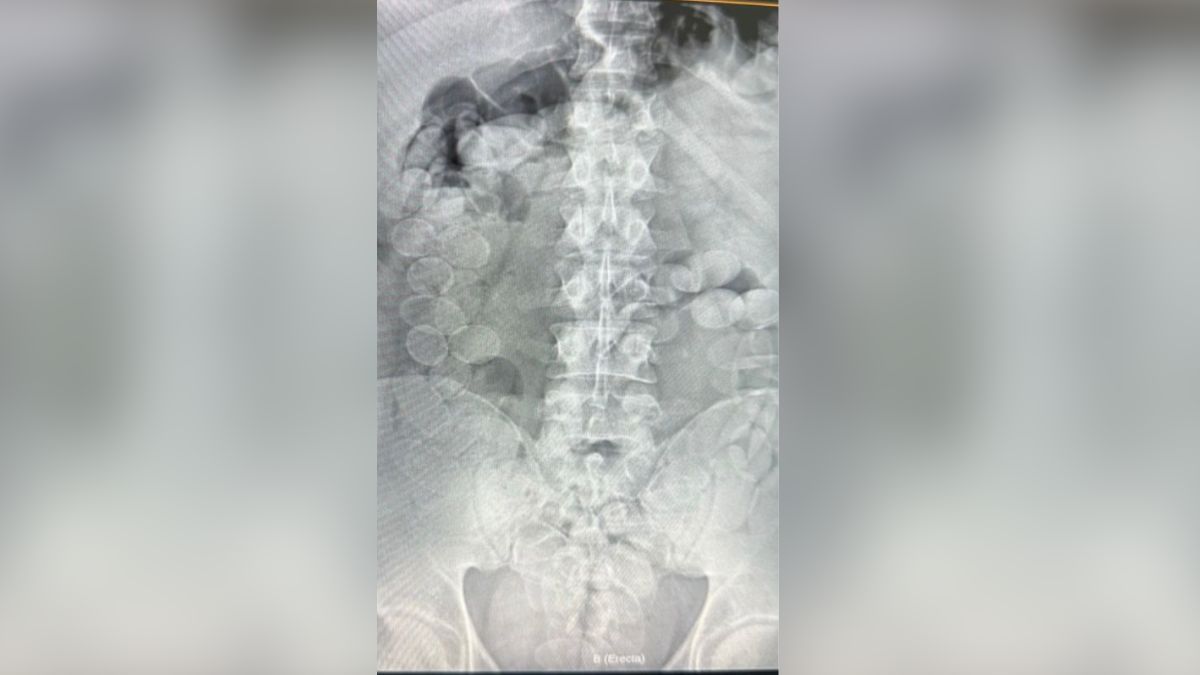

Las dos personas mostraron signos de descompostura, por lo que fueron trasladados a un hospital local. Allí se le realizaron placas radiográficas que confirmaron la sospecha: dentro de sus cuerpos tenían entre 80 y 90 cápsulas de cocaína cada uno.

Tras remover la droga, se constató que cada uno cargaba con más de un kilo de cocaína.